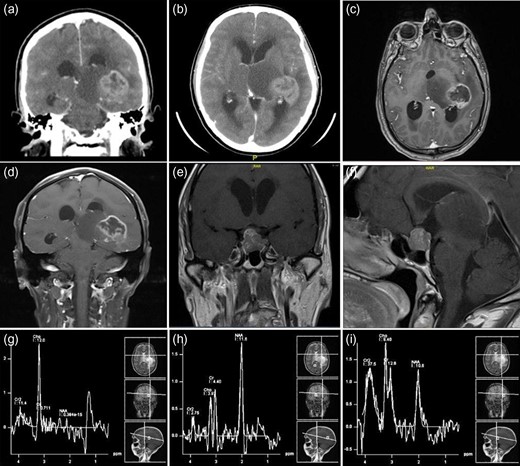

Radiographic studies showed a centrally necrotic peripherally enhancing mass lesion in the left posteromedial temporal lobe, measuring 3.3 × 3.6 cm2. The non-enhancing component of the tumor extended to the left thalamus. There was a slight signal abnormality in the right thalamus. The tumor itself had a central hemorrhagic component as well. There was an apparent obstruction at the level of the cerebral aqueduct and the third ventricle resulting in a moderate acute hydrocephalus involving the lateral ventricles. The fourth ventricle remained decompressed (Fig. 1a–d).

Preoperative neuroimaging of the patient—CT (a and b) and MRI ((c–f )—with contrast enhancement), showing a centrally necrotic peripherally enhancing mass lesion in the left posteromedial temporal lobe representing glioblastoma. The non-enhancing component of the tumor extended to the left thalamus. Another sellar and suprasellar mass lesion representing a pituitary macroadenoma. (g–i) The MR spectroscopy shows a very low N-acetylaspartate (NAA) and high choline keeping up with a malignant tumor.

There was another sellar and suprasellar mass lesion with extension into the right cavernous sinus measuring 1.7 × 1.6 cm2 in the anteroposterior and craniocaudal dimensions, respectively, representing a pituitary macroadenoma. No significant midline shift was noted. The posterior fossa structures were grossly unremarkable. The final impression was an aggressive looking mass lesion involving the left posteromedial temporal lobe and adjacent left thalamus (Fig. 1e and f).

The MR spectroscopy showed a very low N-acetylaspartate (NAA) and high choline keeping up with a malignant tumor (Fig. 1g–i). A contrast-enhanced chest–abdomen, and pelvis CT scan showed no metastasis, lymphadenopathy or any other lesions.